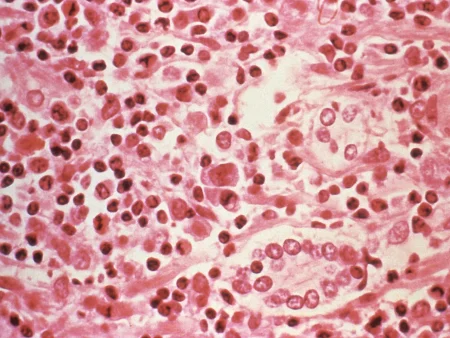

السعال الديكي هو عدوى بكتيرية شديدة العدوى تصيب الجهاز التنفسي، وتنتشر عبر الرذاذ المتطاير الناتج عن السعال والعطس. وفقًا للجنة الألمانية، يعتبر الرضع دون سن ستة أشهر الأكثر عرضة للإصابة بهذا المرض، حيث يمكن أن يتسبب في مضاعفات خطيرة. تشمل هذه المضاعفات كسورًا في الضلوع، والالتهاب الرئوي، وحتى تلف في الدماغ في حالات نادرة.

يبدأ السعال الديكي عادةً بأعراض تشبه أعراض البرد العادي، مثل سيلان الأنف والحمى الخفيفة. ثم يتطور إلى نوبات سعال شديدة تتميز بصوت “ديك” مميز عند الشهيق. يمكن أن تستمر هذه النوبات لعدة أسابيع أو حتى أشهر، مما يؤدي إلى الإرهاق الشديد.

تتراوح نسبة الوفيات بين الأطفال دون سن ستة أشهر المصابين بالسعال الديكي إلى حوالي واحد بالمائة، مما يؤكد على أهمية الوقاية منه. بالإضافة إلى ذلك، يمكن أن يعاني الأطفال المصابون من تشنجات أو توقف مؤقت في التنفس.

بالإضافة إلى ذلك، قد يكون هناك بعض التحديات في تشخيص السعال الديكي في المراحل المبكرة، حيث يمكن أن تتشابه أعراضه مع أعراض أمراض الجهاز التنفسي الأخرى. لذلك، من المهم إجراء الفحوصات المخبرية اللازمة لتأكيد التشخيص.